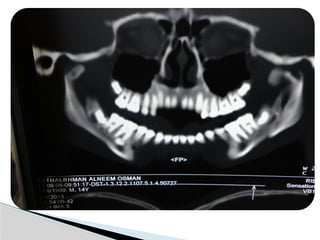

Conventional Radiology

At least 2 views at right angle to each other.

Mandibular series: PA, Lateral oblique or

panoramic, & Towne’s view (projects condyle

below mastoid process).

CT

Significant displacement or dislocation,

mechanical obstruction, mult trauma pt, &

intracapsular fracture.

MRI

St injuries: effusion, visualization of disc.

Imaging

Conventional Radiology At least2 views at right angle to each other. Mandibular series: PA, Lateral oblique or panoramic, & Towne’s view (projects condyle below mastoid process). CT Significant displacement or dislocation, mechanical obstruction, mult trauma pt, & intracapsular fracture. MRI St injuries: effusion, visualization of disc. Imaging